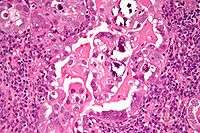

| Micrograph of uterine serous papillary carcinoma. H&E stain. | |

Histopathologically, uterine serous carcinomas is typically characterized by (1) nipple-shaped structures (papillae) with fibrovascular cores (2) marked nuclear atypia (irregularies in the nuclear membrane, enlarged nuclear size), (3) psammoma bodies and (4) cilia.